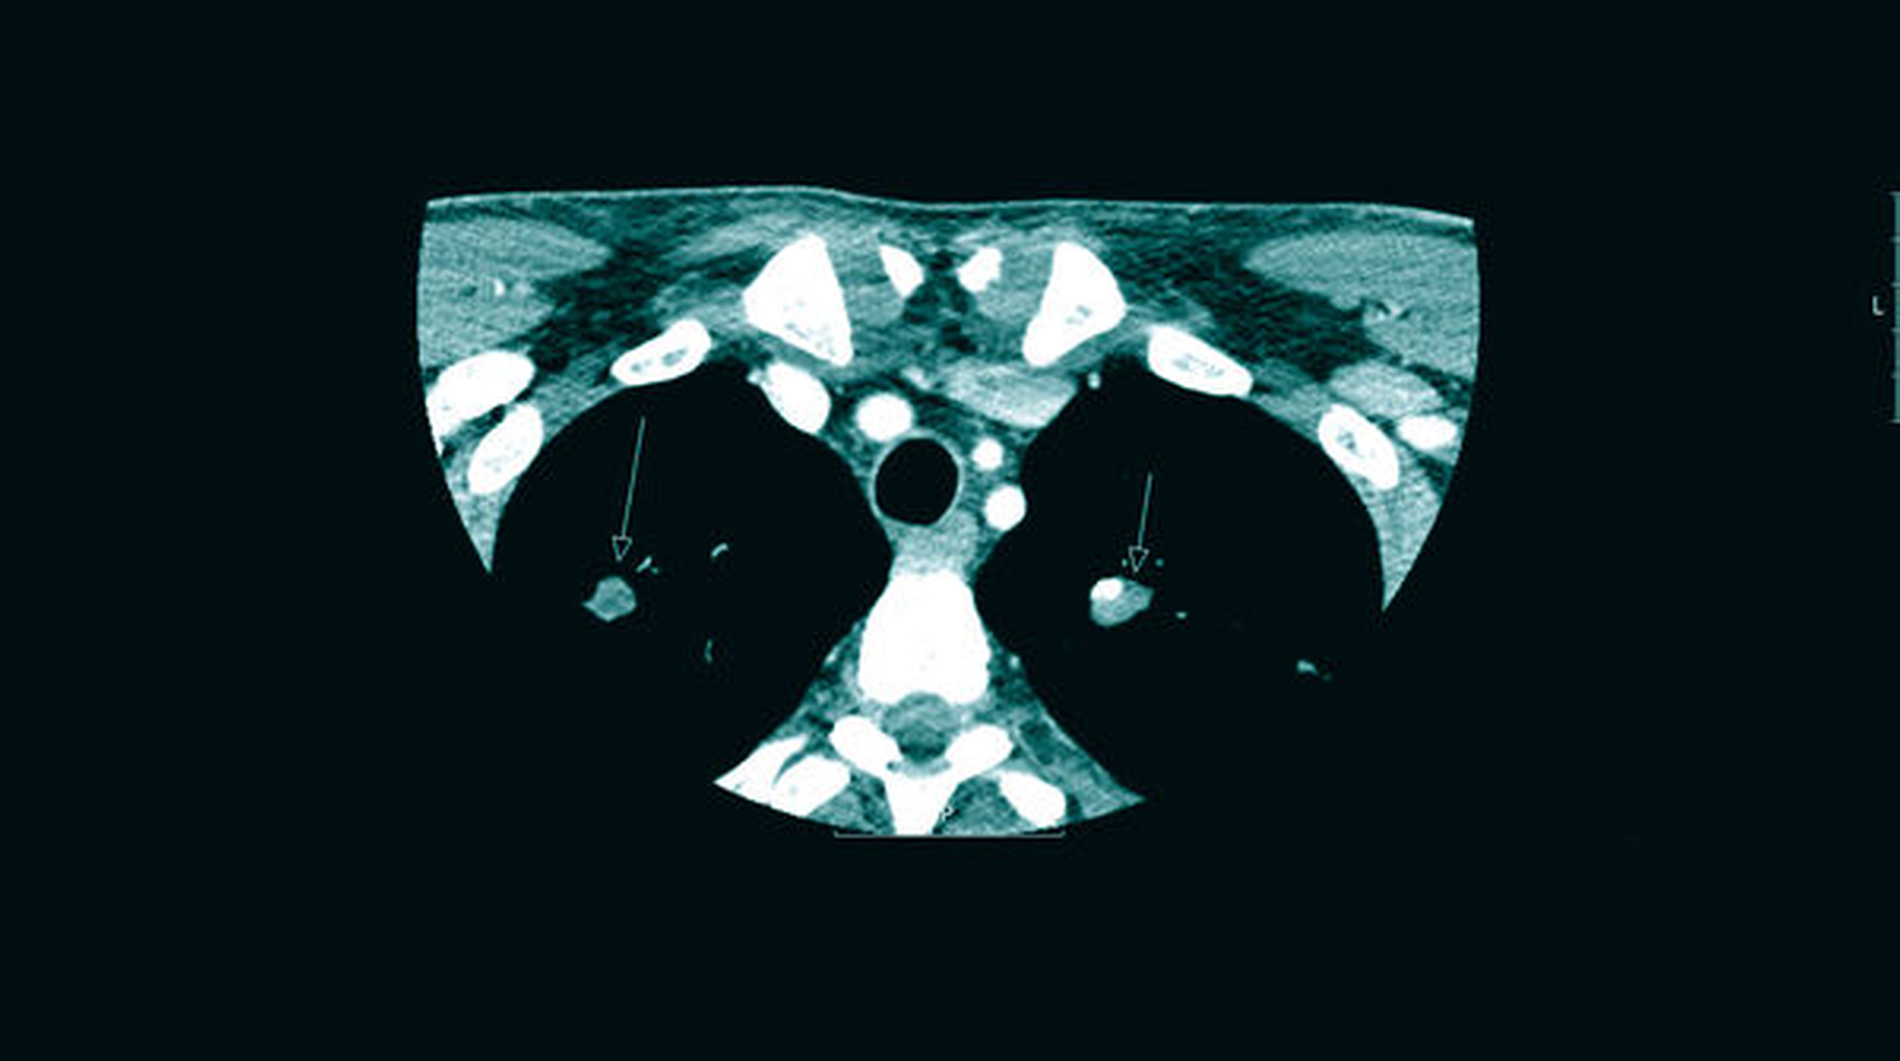

Die postoperative Bildgebung (Halbseiten-OPTG) zeigt die Extraktionsalveolen 46 und 47 ohne Anhalt auf Wurzel- oder Materialreste ebenso wie die eingelegten Drainageröhrchen (Abbildung 2). Während des postoperativen Heilungsverlaufs war die Schwellung nur langsam regredient und der Abgang putriden Sekrets über die extraorale Wunde weiterhin stark, so dass eine Computertomografie (CT) des Halses zum Ausschluss eines Wurzelrests, einer Fraktur oder einer Ausbreitung durchgeführt wurde. In dieser fielen nebenbefundlich circa 10 mm messende Verdichtungen in beiden Lungenoberlappen im Sinne punktuell verkalkter Kavernen auf (Abbildung 3).